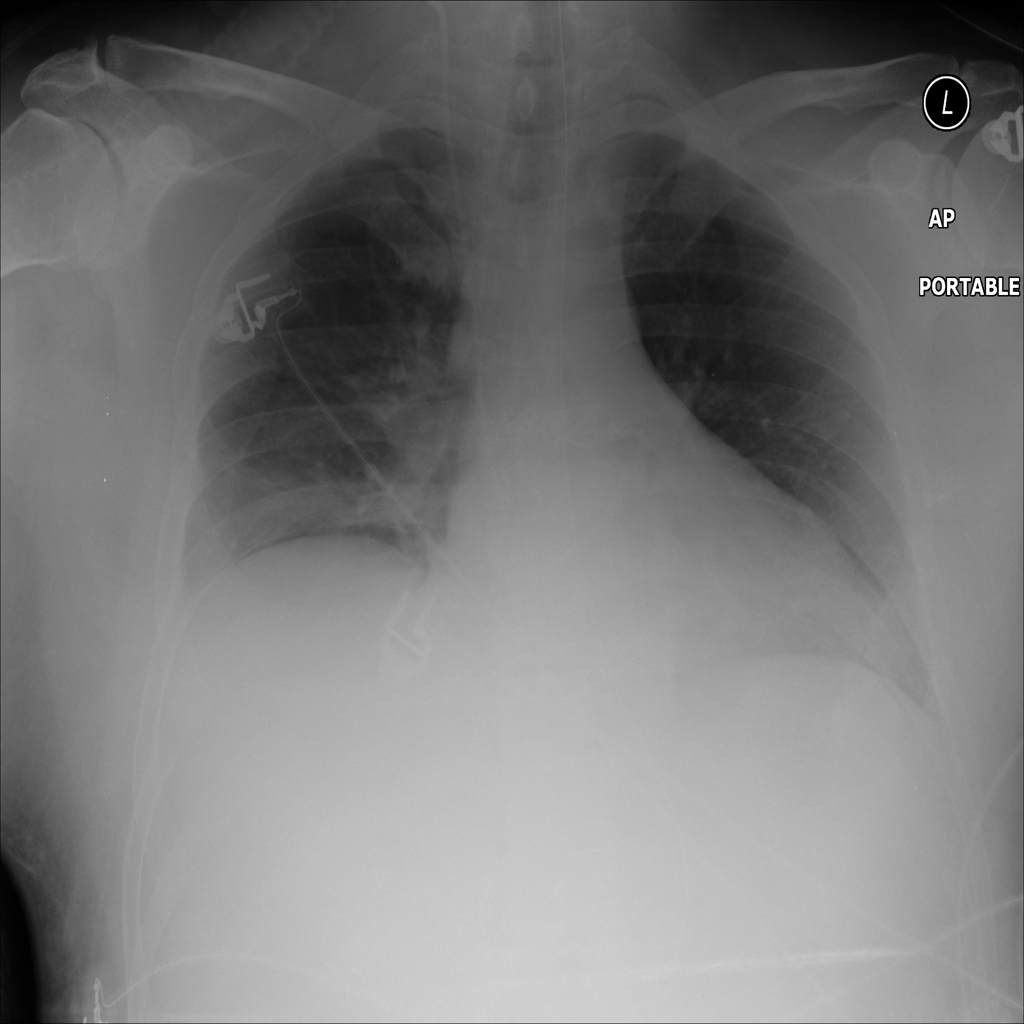

PAT-F3E7 · IMG-000Cardiomegaly

PAT-F3E7 · IMG-000

PA